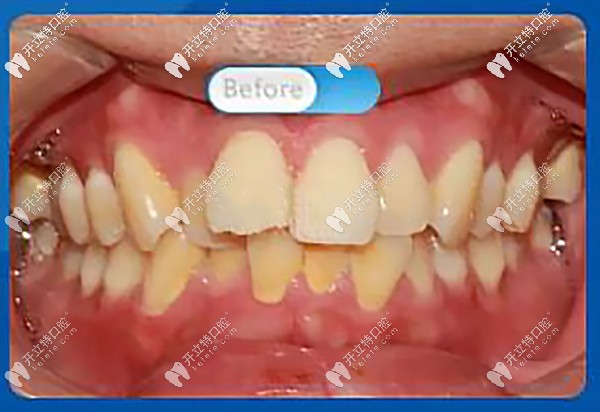

托槽矯正前,正面看牙齒屬于重度擁擠,微笑時(shí),明顯看到前牙凸出,凸嘴齙牙明顯

正面看牙齒屬于重度擁擠

醫(yī)生:“從口內(nèi)正面照可以看到上牙列前牙前突,上下牙列不齊擁擠,牙中線不齊,上下咬合不協(xié)調(diào),磨牙深覆蓋?!?br/>